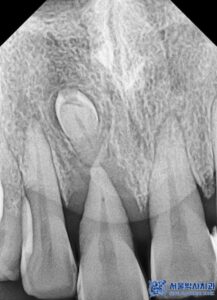

결국, 해당 치아는 살릴 수 없는 상태였기에

발치를 진행하기로 하였으며,

치근낭(치아 뿌리 주변에 형성된 염증 조직)도

함께 제거하고 염증으로 잇몸뼈가 녹은 부위는

잇몸뼈를 이식하여 잇몸이

꺼져 보이지 않도록 진행하기로 하였습니다.